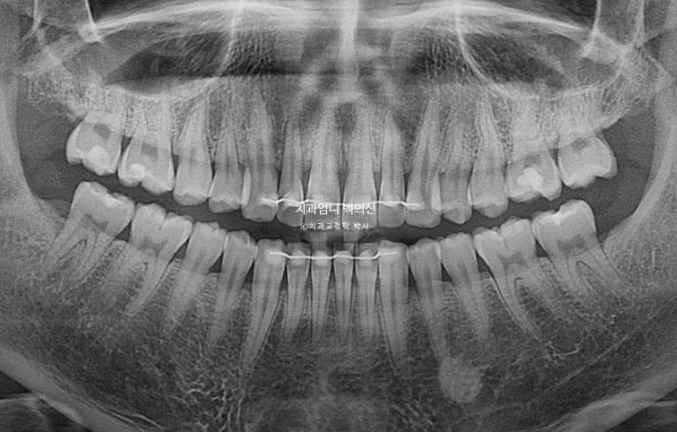

25년 2월 교정상담을 위해 오신 분입니다.

앞니가 기울어져 있고 중심선이 안 맞습니다.

어금니교합은 좋은 편입니다.

어금니 배열도 좋은 편이라 앞니 부분교정 권유드렸습니다.

치근흡수는 없고 뿌리 평행도도 좋습니다.